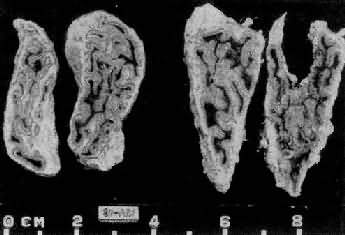

1.垂体性Cushing综合征 主要由垂体ACTH细胞腺瘤所引起,少数由于下丘脑异常分泌过多的促皮质释放因子(CRF)所致。血清中ACTH增高,双侧肾上腺呈弥漫性中度肥大,重量可达20g(正常8g左右),切面皮质厚度可超过2mm,呈脑回状。镜下主要是网状带及束状带细胞增生(图15-13、图15-14)。

肾上腺皮质弥漫增生(大体)

图15-13 肾上腺皮质弥漫增生(大体)

肾上腺肥大,皮质弥漫性增厚,切面呈脑回状